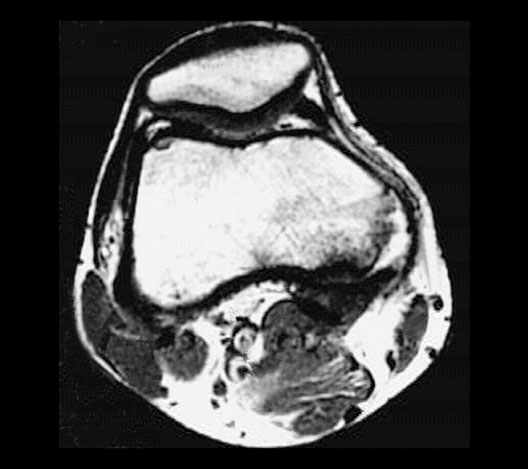

Roll mouse over image to display labels.

1. Popliteal artery

2. Popliteal vein

3. Patella

4. Femur

5. Tendon of popliteus muscle

6. Great saphenous vein

7. Sartorius muscle